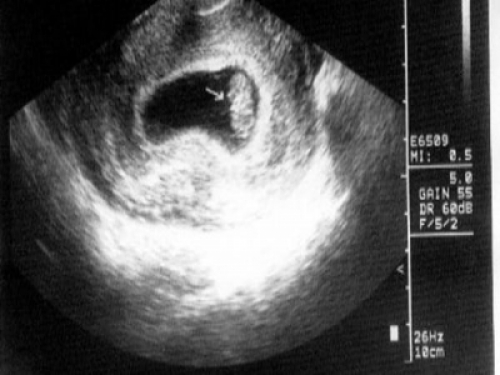

1. 男性胎兒會在母親子宮里勃起

研討發現,男女嬰兒在子宮內都可能有手淫的舉措,

超聲波圖像也曾抓拍到男嬰的勃起圖片。

不過只有男性能在X光片上看出來,原因嘛…你們懂的。